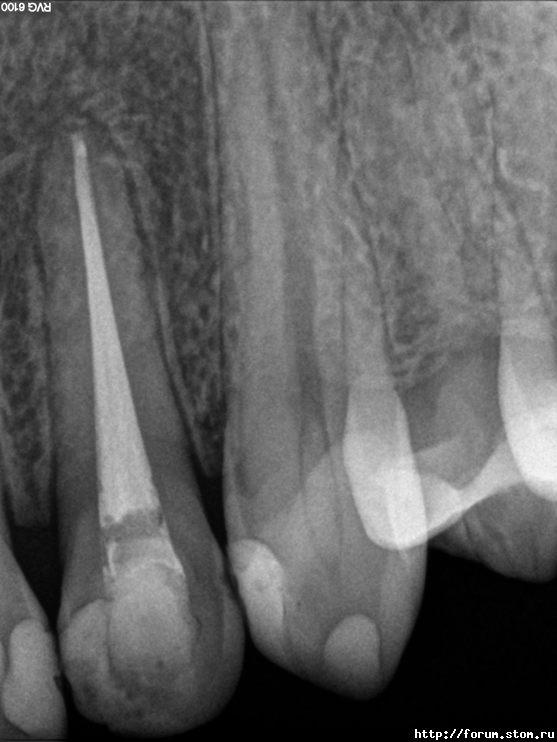

natikkk Опубликовано 6 ноября, 2011 Автор Поделиться Опубликовано 6 ноября, 2011 Делюсь радостью Тот же пациент через 10.5 месяцев после завершения лечения, жалобы отсутствуют Ссылка на комментарий

Снежана Опубликовано 6 ноября, 2011 Поделиться Опубликовано 6 ноября, 2011 прекрасный результат. поздравляю доктор! Ссылка на комментарий

Джима Опубликовано 7 ноября, 2011 Поделиться Опубликовано 7 ноября, 2011 Здорово как! Как будто не этот зуб к хирургу почти отправили. Ссылка на комментарий

natikkk Опубликовано 7 ноября, 2011 Автор Поделиться Опубликовано 7 ноября, 2011 Отличная работа! Сколько пац ходил с каласептом и чем потом пломбировали?Еще раз спасибо! На Каласепте в общей сложности ходил месяца 1.5, меняла его за это время вроде раза 3, мыла, звучила. Окончательная пломбировка- Термафил Ссылка на комментарий